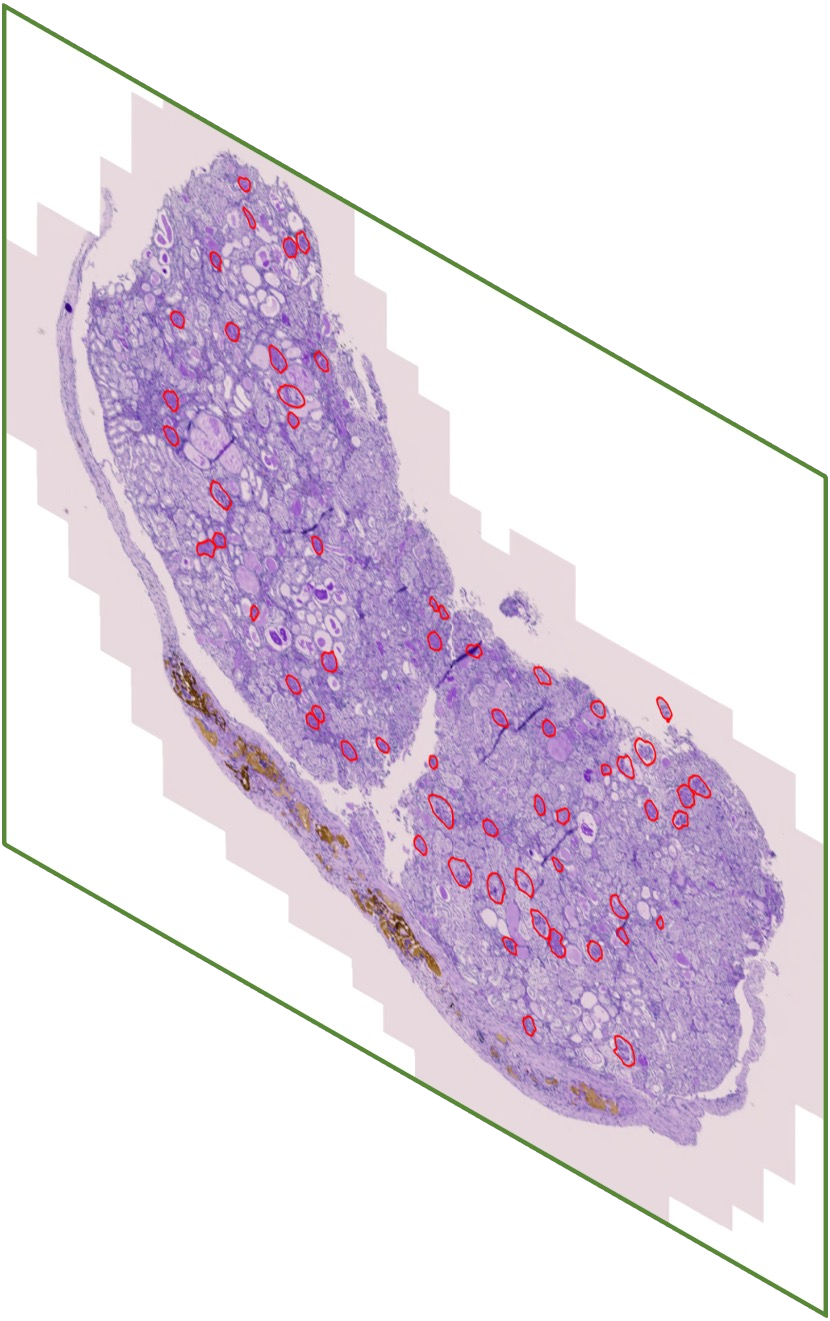

In digital pathology, the traditional method for deep learning-based image segmentation typically involves a two-stage process: initially segmenting high-resolution whole slide images (WSI) into smaller patches (e.g., 256x256, 512x512, 1024x1024) and subsequently reconstructing them to their original scale. This method often struggles to capture the complex details and vast scope of WSIs. In this paper, we propose the holistic histopathology (HoloHisto) segmentation method to achieve end-to-end segmentation on gigapixel WSIs, whose maximum resolution is above 80,000$\times$70,000 pixels. HoloHisto fundamentally shifts the paradigm of WSI segmentation to an end-to-end learning fashion with 1) a large (4K) resolution base patch for elevated visual information inclusion and efficient processing, and 2) a novel sequential tokenization mechanism to properly model the contextual relationships and efficiently model the rich information from the 4K input. To our best knowledge, HoloHisto presents the first holistic approach for gigapixel resolution WSI segmentation, supporting direct I/O of complete WSI and their corresponding gigapixel masks. Under the HoloHisto platform, we unveil a random 4K sampler that transcends ultra-high resolution, delivering 31 and 10 times more pixels than standard 2D and 3D patches, respectively, for advancing computational capabilities. To facilitate efficient 4K resolution dense prediction, we leverage sequential tokenization, utilizing a pre-trained image tokenizer to group image features into a discrete token grid. To assess the performance, our team curated a new kidney pathology image segmentation (KPIs) dataset with WSI-level glomeruli segmentation from whole mouse kidneys. From the results, HoloHisto-4K delivers remarkable performance gains over previous state-of-the-art models.